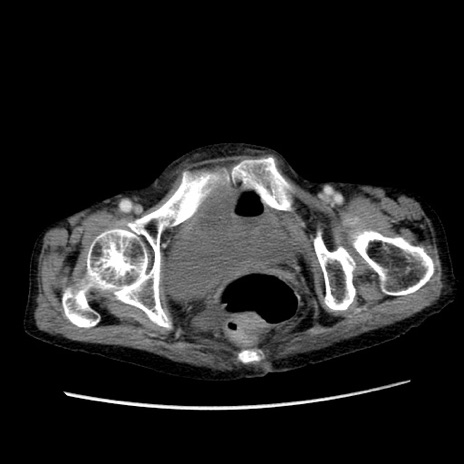

冠状断像

症例25(横断像)

【症例】80歳代女性

【主訴】胸のつかえ感

【現病歴】約9時間前に食後から胸のつかえた感じあり、嘔吐あり、来院。

【既往歴】胃癌(全摘)、胆摘、虫垂炎

【身体所見】心窩部に圧痛あり、反跳痛なし。

【データ】WBC 5700、CRP 0.05